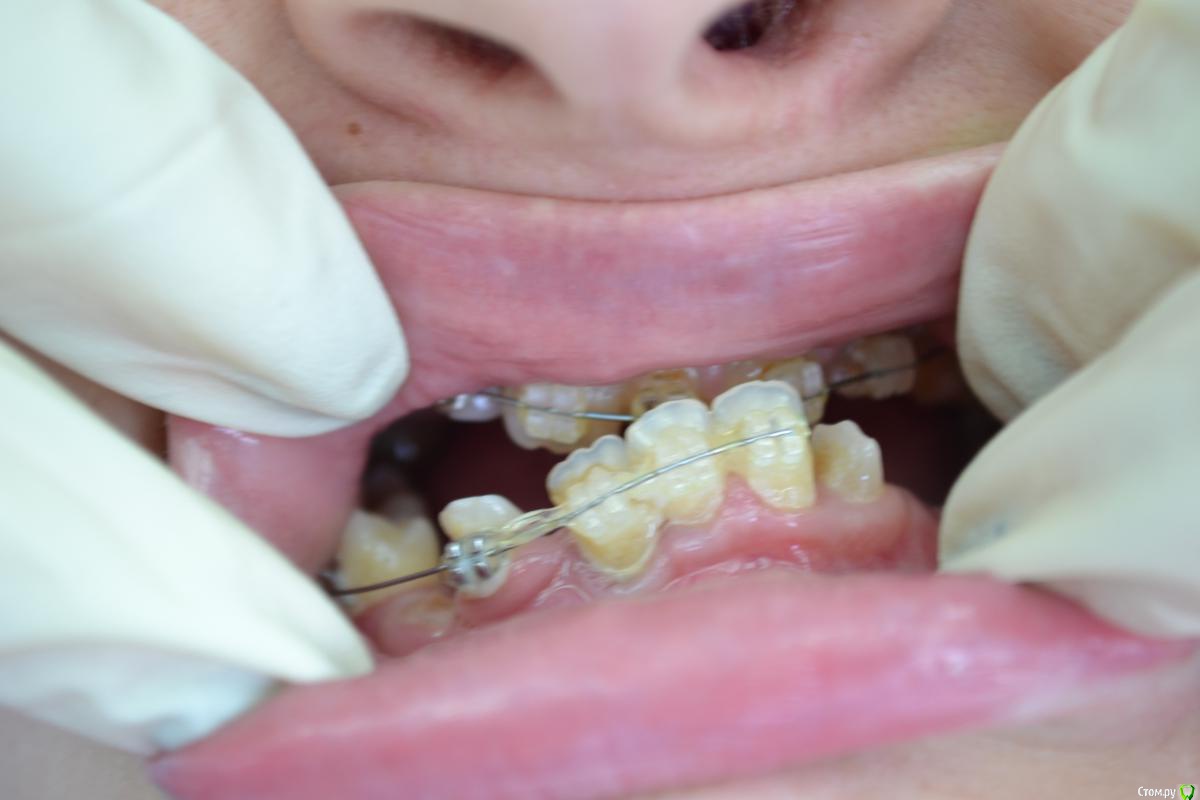

nikor117 Опубликовано 14 октября, 2015 Поделиться Опубликовано 14 октября, 2015 Здравствуйте, уважаемые коллеги.Извиняюсь за качество фото. Хотелось бы помочь пациентке 28 лет. В общем ситуация видна по фото. Сам я ортопед опыта в таких ситуациях нет, возможно подскажете куда ей стоит обратиться. Заранее спасибо. Если нужна дополнительная информация скажите постараюсь выложить. Ссылка на комментарий

nikor117 Опубликовано 14 октября, 2015 Автор Поделиться Опубликовано 14 октября, 2015 Возможность красиво улыбаться, с ее слов на ортодонтии она уже порядка 8 лет, брекеты стоят 1.5 или 2 года, сама врач, сложность ситуации представляет, хочет услышать совет Ссылка на комментарий

Yana guapa Опубликовано 14 октября, 2015 Поделиться Опубликовано 14 октября, 2015 эти фото были ведь на соседнем форуме "...." . там были советы, и хирурги и ортодонты отписывались. причем не так давно. и фото были без брекетов, до начала лечения (около 6 месяцев назад). не похоже на 1.5 года с брекетами здесь . тем, что у нее на зубах стоит сейчас - не помочь это точно. 4 Ссылка на комментарий

Monkey Опубликовано 18 октября, 2015 Поделиться Опубликовано 18 октября, 2015 (изменено) и мне, пожалуйста у пациентки похоже синдром Крузона Изменено 18 октября, 2015 пользователем Monkey 1 Ссылка на комментарий